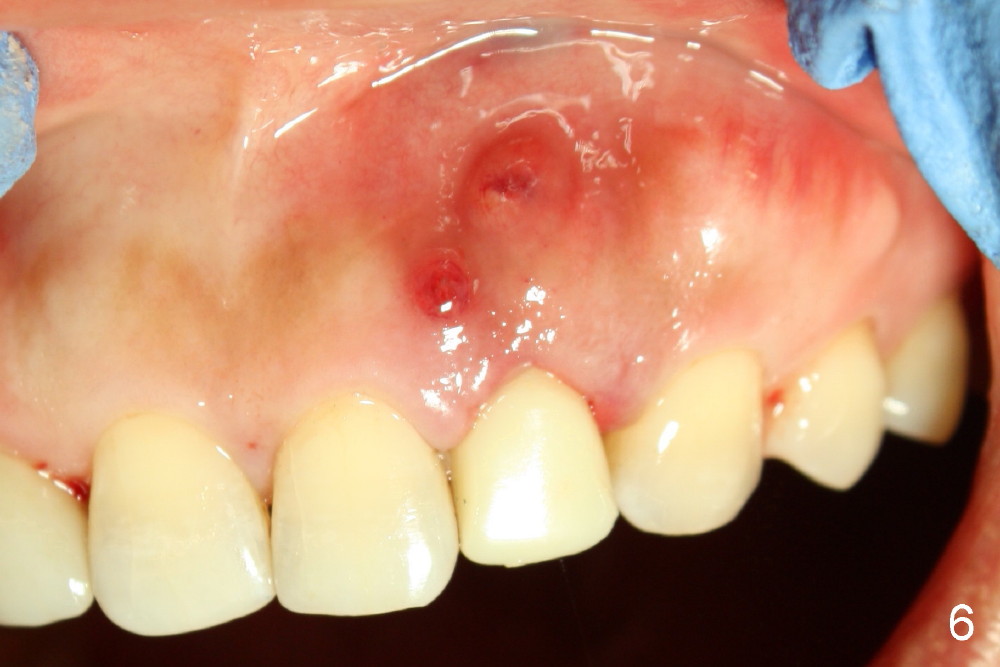

A 49-year-old lady has failed endo on the upper left lateral incisor (Fig.1,2). A gutta percha inserted to the buccal fistula (Fig.1 >) shows a mesial defect (Fig.2<). There is a large buccal apical defect, corresponding to the lesion shown in Fig.2 *, when the affected tooth is extracted. After thorough debridement and Clindamycin soaking, osteotomy is initiated in the palatal wall of the socket. Demineralized freeze dry cancellous bone graft is placed in the buccal defect. A 4x20 mm gingiva-level tapered implant is placed with insertion torque 50 Ncm (Fig.3). A 3x5 mm 20 ° offset abutment is inserted and cemented (Fig.4,5). A retentive groove is prepared on the abutment and the underlying implant; chamfer margin placed on the implant (Fig.4,5). A provisional is fabricated and cemented temporarily (Fig.6,7). Excess cement is removed, followed by removal of gingival retraction cord. There is no contact in centric and non-centric occlusion.

Within one week, the infection resolves (Fig.8,9).